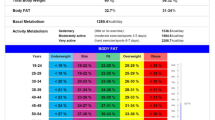

An eight-polar tactile-electrode impedance meter (InBody 720, Biospace, Seoul, Korea) was used to assess the body composition and simultaneously recorded body weight, FFM, total body water, regional fat mass, and BMR [18].

Between August 2010 and December 2012, all participants were enrolled from the rural community from southern Taiwan. A total of 363 postmenopausal women over the age of 50 were included in this study. Based on the WHO osteoporosis definition, 211 subjects whose T-score > −2.5 were classified as non-osteoporosis group and 152 subjects whose T-score < −2.5 as osteoporosis group. The subjects’ demography is shown in Table 1. The average subjects’ age is 64.1 years, and body mass index (BMI) is 24.7 kg /m2. The women had a mean T-score of the femur neck and spine of respectively −1.9 ± 1.0 and −1.8 ± 1.4. Their mean FFM, FM, and FM ratio are respectively 38 ± 4 kg, 21.2 ± 6.3 kg, and 35 ± 7%, while the mean of BMR is 1182.7 ± 88.9 kcal. Age, height, weight, BMI, femur neck T-score (FNTS), spine T-score (STS), FFM, FF, and BMR had significant differences between the two groups. So, we assessed the relationship between BMD T-score (femur neck and spine) and other variables by Pearson correlation analysis. As shown in Table 2, age is negatively correlated with FNTS and STS while other variables are positively correlated with FNTS and STS (p < 0.01 for all). The correlation coefficient of FFM, FM, FM ratio, and BMR with femur neck T-score was 0.373, 0.266, 0.165, and 0.369, respectively, while with spine T-score 0.350, 0.251, 0.166, and 0.352, respectively. Meanwhile, we performed a multivariate logistic regression analysis of osteoporosis that showed age, FM ratio, and BMR were significant factors (Supplemental Table 1).